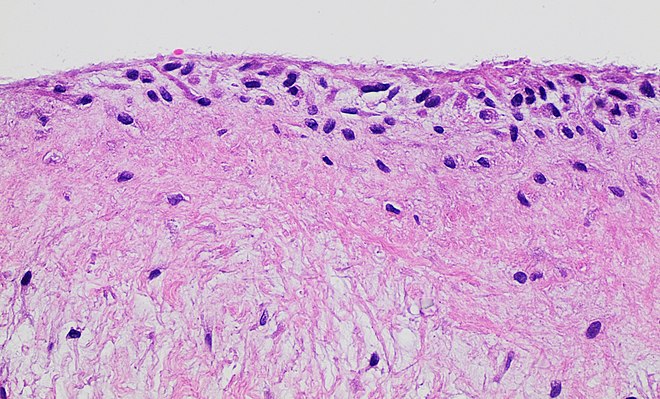

La sinovial es una membrana delgada que recubre la superficie interior de la cápsula articular. Se inserta en los bordes del revestimiento cartilaginoso de las superficies articulares y comparte un origen embriológico común con el cartílago. En casos en los que la cápsula se inserta a cierta distancia de la superficie articular, la sinovial tapiza toda la superficie ósea interpuesta, formando lo que se conoce como receso articular.

La sinovial puede presentar pliegues de diferentes tamaños en el interior de la articulación, conocidos como pliegues sinoviales. Estos pliegues se encuentran frente a las interlíneas articulares y llenan los espacios libres dentro de la articulación.

La sinovial es la parte más vascularizada de la articulación y cumple una función importante en la producción de líquido sinovial. Este líquido es transparente y se encuentra en cantidades escasas en condiciones normales. Está compuesto principalmente por agua, proteínas, mucina, trazas de grasas y sales minerales. También pueden encontrarse células desprendidas del cartílago y de la propia membrana sinovial en el líquido sinovial.